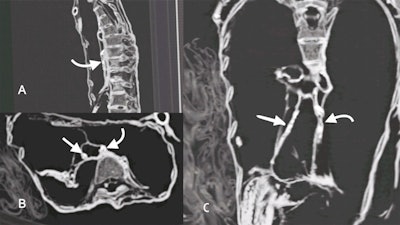

She noted that definite atherosclerotic changes are visible as high-density areas of calcification within the walls of identifiable arteries: right and left carotid bulbs, right and left coronary arteries, abdominal aorta, superior mesenteric artery, coeliac artery, bilateral iliac, femoral and peripheral leg arteries. Also evident was mild lateral curvature of the dorsal spine with its convexity to the left (scoliosis); no structural abnormalities of the spine or anomalous vertebrae could be seen.